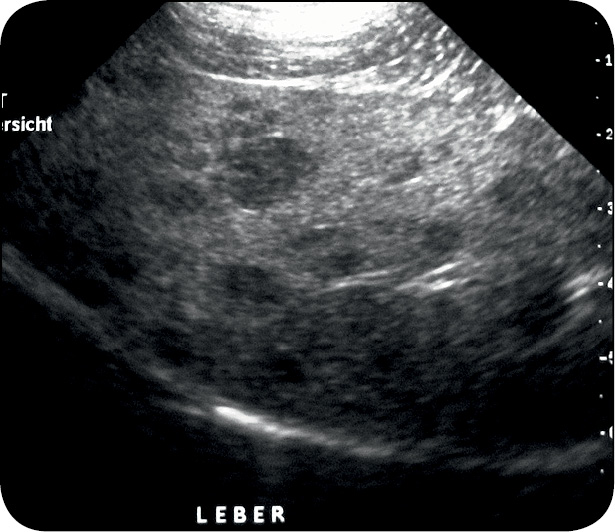

W oparciu o diagnostykę różnicową przeprowadzono szereg badań (tab. 1). Badanie cytologiczne skóry wykazało ropne zakażenie ziarniakami. W posiewach wyhodowano Staphylococcus intermedium. Badanie biochemiczne surowicy wykazało obniżony poziom mocznika oraz lekko podwyższone AP i ALT (tab. 2). W badaniu ultrasonograficznym jamy brzusznej, w wątrobie widoczne były obszary o średnicy do 15 mm otoczone przez mniej echogenne pasma, co przypominało wyglądem ser szwajcarski (ryc. 4), s. 30. Dodatkowo pobrano wiele próbek – bioptatów z chorobowo zmienionych miejsc na skórze. Naskórek był przerośnięty ze znacznym rogowaceniem warstwy powierzchownej o charakterze parakeratozy, z wakuolizacją keratynocytów w warstwie kolczystej i rozrostem komórek w warstwie podstawnej naskórka (ryc. 5, 6), s. 30. Opisanym zmianom towarzyszył rozproszony naciek komórek zapalnych (limfocytów i komórek plazmatycznych). Na tej podstawie postawiono wówczas rozpoznanie MEN, wtórnego ropnego zapalenia skóry oraz wyrównanego zapalenia wsierdzia zastawki mitralnej.